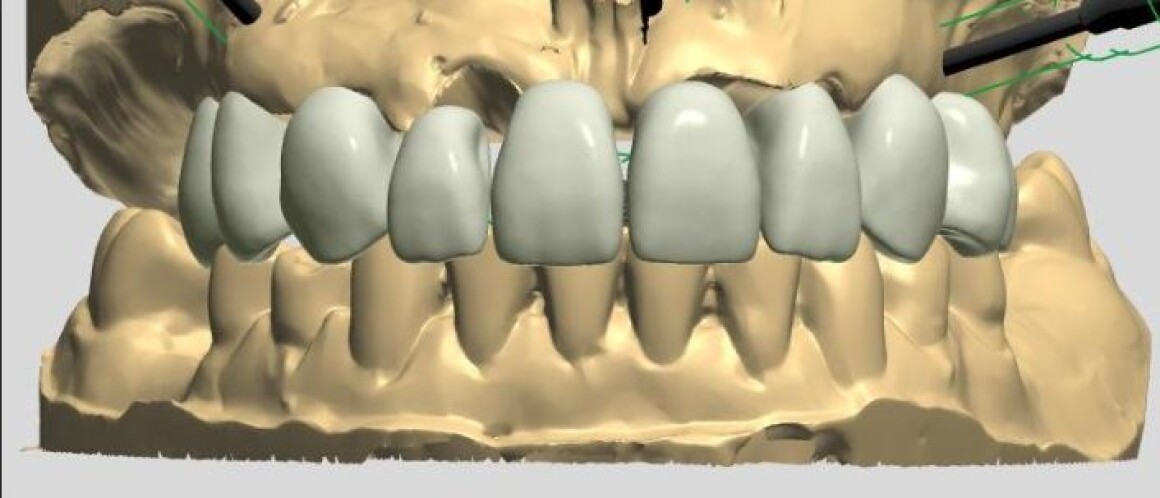

• Планирование имплантации

• Изготовление временных конструкций на имплантантах

• Изготовление шаблонов для операции